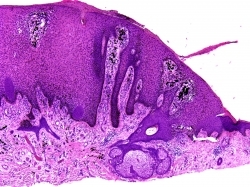

Pilomatrixoma (Calcifying epithelioma of Malherbe): Found on the head, neck and upper extremities in the first 2 decades of life. Typically solitary but multiple pilomatricomas arise in several syndromes. Even in isolation these tumors may arise due to activating mutations in the beta-catenin gene. Histologically: This tumor consists of two major cell types plus an intermediate or transitional cell type. Initially the tumor is more cystic with the cells at the periphery of the tumor that are more basophilic with indistinct cell borders and little cytoplasm. The cells have hyperchromatic nuclei and often normal mitoses can be appreciated. Centrally there are eosinophilic “ghost or shadow†cells which are cells that have undergone terminal differentiation. These cells have more distinct borders, increased cytoplasm but only a ghost of a nucleus. Then there are cells that reside somewhere in between these two cell types. The proportion of these cells varies depending on the stage of the lesion; i.e younger lesions have more basophilic cells and appear more cystic, older lesions have a greater component of ghost cells and up to 20% of lesions on removal are completely composed of ghost cells.

Fig 2 Pilomatrixoma. Low-power view showing a circumscribed basophilic tumor surrounded by compressed fibrous tissue.

Fig 3 Pilomatrixoma. The basaloid cells have basophilic cytoplasm and regular oval or round vesicular nuclei with a prominent nucleolus. Note that there is brisk mitotic activity. This is a common feature and should not be taken to imply malignancy.

Fig 4 Pilomatrixoma. High-power view of typical eosinophilic anucleate “ghost” cells.

Fig 5 Pilomatrixoma. Stippled basophilic calcification is invariable in established lesions.

Fig 6 Pilomatrixoma. Many old lesions show bone formation sometimes accompanied by marrow spaces.